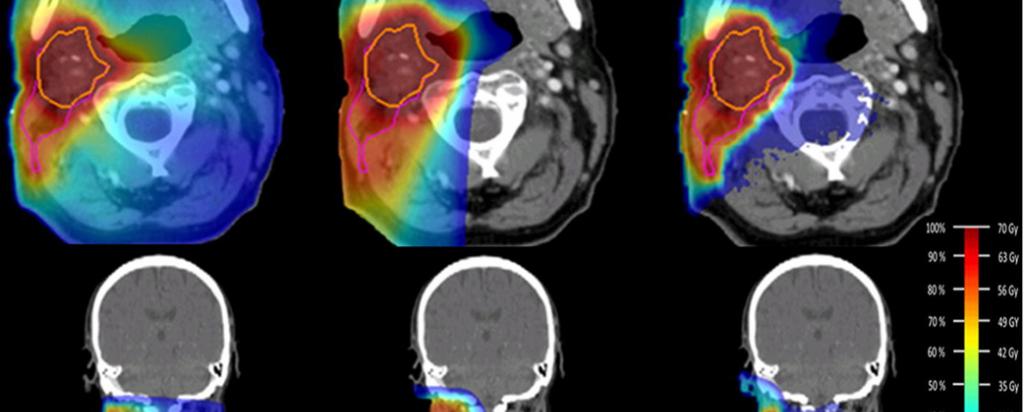

Heavy ions deliver the maximum dose at the site of the tumour, since they deposit their energy at the very end of their path through matter (known as the Bragg peak) and largely spare the surrounding healthy tissue.

“When the patient is receiving therapy, you can produce PET images of the secondary particles, positron-emitting radionuclides, which are created by the primary beam due to nuclear fragmentations,” said Ahmed.

“What you see and quantify in the image allows you to determine the depth at which the dose was deposited, and confirm that it conforms to the tumour site,” said Ahmed.

Heavy ion therapy is quite sensitive to spatial range uncertainties due to its very steep dose profile, research such as Ahmed's is supporting the development of new methods for direct dose estimation based on the detection of secondary fragments.